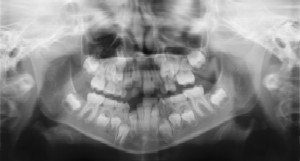

Digital radiographs are a vital and necessary part of your child’s diagnostic process. Without them, certain dental conditions can and will be missed. Digital radiographs detect more than cavities. For example, radiographs may be needed to survey erupting teeth, diagnose bone diseases, evaluate the results of an injury, or plan orthodontic treatment. Radiographs allow dentists to diagnose and treat health conditions that cannot be detected during a clinical examination. If dental problems are found and treated early, dental care is more comfortable for your child and more affordable for you.

The American Academy of Pediatric Dentistry recommends radiographs and examinations every six months for children with a high risk of tooth decay. On average, most pediatric dentists request radiographs approximately once a year. Approximately every three years it is a good idea to obtain a panoramic film.

Pediatric dentists are particularly careful to minimize the exposure of their patients to radiation. With contemporary safeguards, the amount of radiation received in a dental X-ray examination is extremely small. The risk is negligible. In fact, the dental radiographs represent a far smaller risk than an undetected and untreated dental problem. Lead body aprons and shields will protect your child. Today’s equipment filters out unnecessary x-rays and restricts the x-ray beam to the area of interest. High-speed film and proper shielding assure that your child receives a minimal amount of radiation exposure.